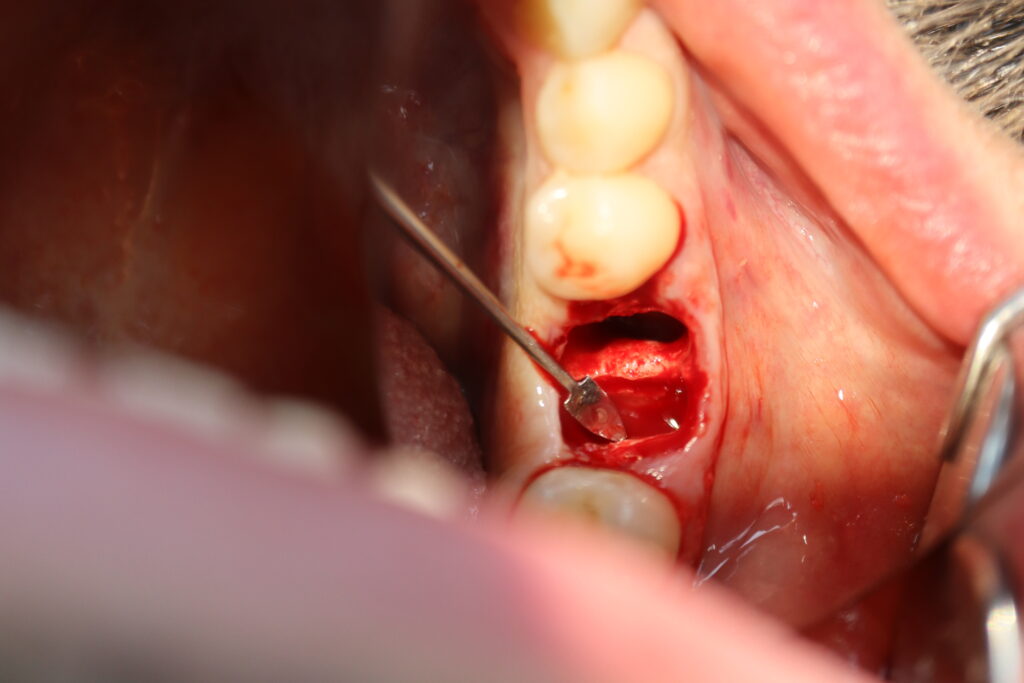

процедура имплантации

Это фото может содержать тяжелый для восприятия контент